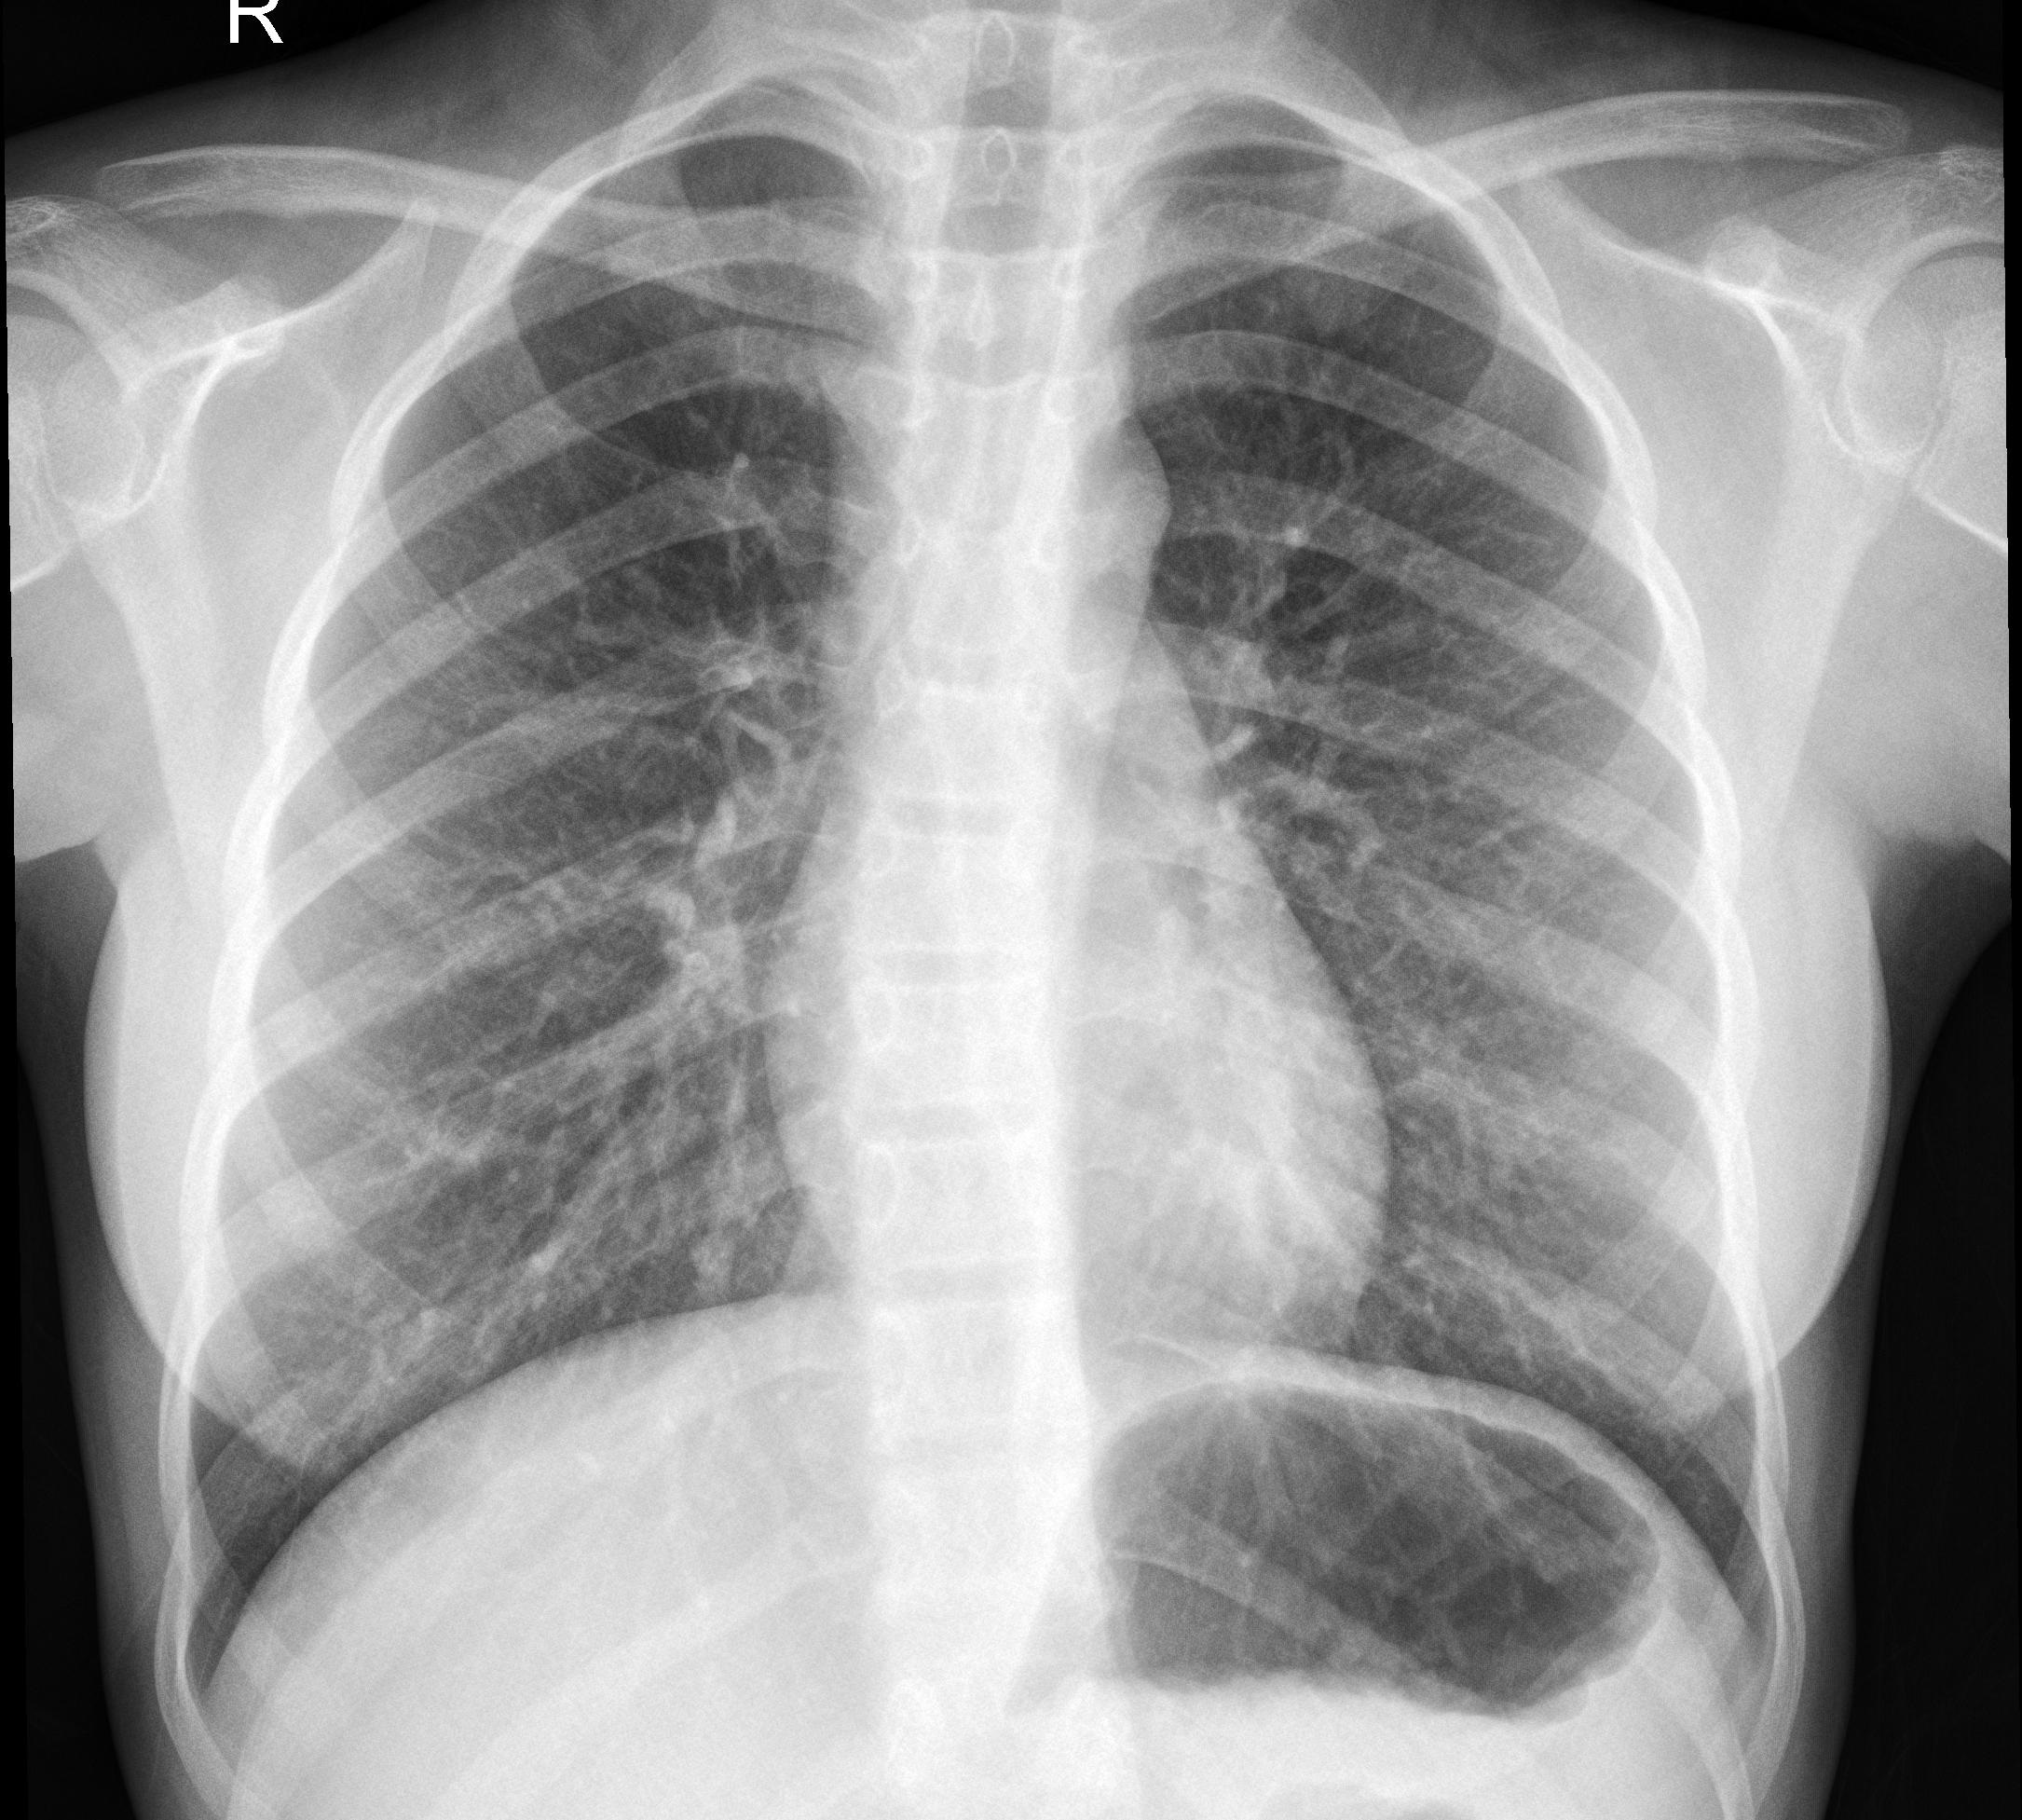

Die Verbreitung der Coronavirus-Erkrankung schritt so schnell voran, dass sie Krankenhäuser in der Diagnose nicht hinterher kamen.Aus diesem Grund wurde die schnelle Produktion der RT-PCR Test-kits von großer Bedeutung und ging in Massenproduktion, was jedoch auch einige Probleme nach sich zog u.a verminderte Genauigkeit und die Unzuverlässigkeit einiger Kits. Studien über die Symptome des Virus ermöglichten eine Kategorisierung der Infizierten. Als Hauptsymptome gelten Fieber und Atembeschwerde bzw. hohes Fieber und Atemstörung als Symptome der Schwererkrankten. Ausgeführte Studie haben gezeigt, dass in den ersten Phasen der Krankheit, Röntgenbilder der Brust ein genaueres Ergebnis liefern als die ältere Methode der Test-Kits. Für diesen Zweck haben wir eine App erstellt, welche durch die Analyse der Röntgenbilder die Krankheit und Ihre unterschiedlichen Phasen präziser erkennbar macht.